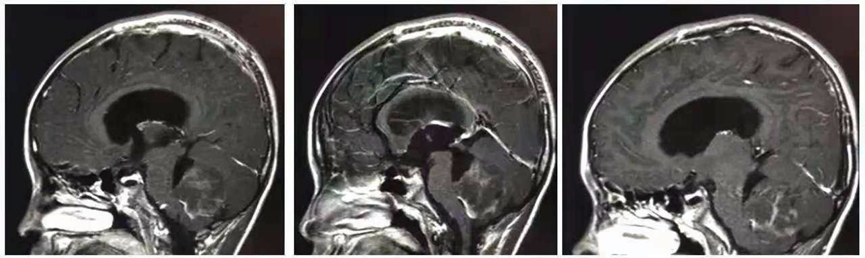

James T.Rutka教授在演讲中与大家共同交流了一个8岁小男孩朱利安战胜脑瘤的故事。发病前,朱利安是一个无忧无虑的孩子,他不知道等待他的将是什么,直到头痛、呕吐等症状频繁出现,家人才发现他脑子里长了肿瘤。一家人也至此开始走上“过山车之旅”,开启了漫长的治疗过程。

幸运的是,朱利安在Rutka教授所在医院加拿大多伦多大学儿童医院(SickKids)接受了一系列治疗,包括较开始由Rutka教授主刀的全切手术以及后续的相关放化疗等。

虽然手术后朱利安的病理结果为髓母细胞瘤,这种恶性肿瘤虽然每10万人中发病才不到1个人,但具有预后差、生长快、易转移的特点。即使手术切除掉肿瘤,3-6个月肿瘤就可能复发,长到原来大小。

而Rutka教授以及SickKids首先用分子生物学方法确定了朱利安的髓母细胞瘤亚型分型,而后制定了手术+放疗+周期性化疗的治疗方案,通过多学科专家科学协作以及联合治疗方法,朱利安的髓母细胞瘤终于得到了遏制。目前,他已与肿瘤和平共处了10年之久,他成长为大人的同时也练就了异于常人的坚强毅力。他的故事在SickKids被广为传颂,他也可以说是SickKids的“抗癌天使”了。